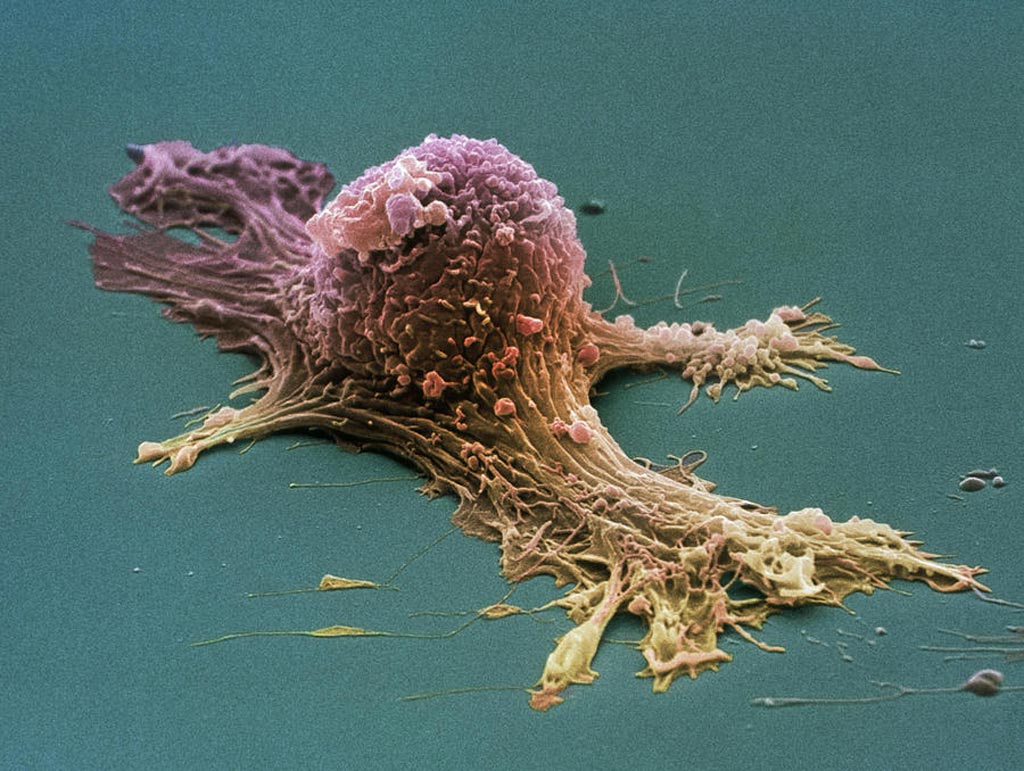

Раковая шишка – это заболевание, которое поражает кожу и слизистые оболочки. Она может возникнуть в различных частях тела и иметь различные внешние проявления. В данной статье мы представляем вам многочисленные фотографии раковых шишек, чтобы вы могли узнать, как они выглядят.

Одной из наиболее распространенных локализаций раковых шишек является лицо. На фото вы можете увидеть различные типы раковых шишек, такие как базалиома, плоскоклеточный рак и меланома. Обратите внимание на характерные признаки каждого типа раковой шишки, такие как изменение цвета, формы и размера.

Раковые шишки могут возникать не только на лице, но и на других частях тела. На фотографиях вы можете увидеть примеры раковых шишек на шее, руках, ногах и туловище. Обратите внимание на различные формы и размеры раковых шишек, а также на их внешний вид.